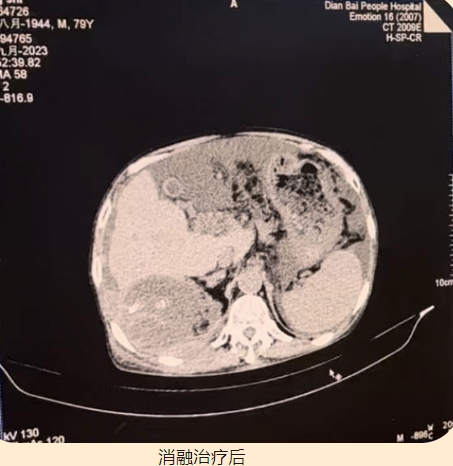

80歲的楊大爺,2016年1月被診斷為“原發(fā)性肝癌”,外院先后共行4次介入治療術(shù),2018年11月和2022年4月期間兩次復(fù)發(fā),再次行介入治療,直至今年因消化道出血并肝性腦病到我院ICU住院治療,盡管治療后病情有所緩解,但身體恢復(fù)很差,反復(fù)腰腹痛,乏力,胃口差,精神疲倦,最后轉(zhuǎn)入腫瘤介入科進(jìn)行進(jìn)一步治療。復(fù)發(fā)肝癌,發(fā)展速度迅猛,生命岌岌可危,加上楊大爺年紀(jì)較大,難以經(jīng)受病情的反復(fù)折磨,家屬更是一籌莫展。急病人所急,想病人所想,我院集中力量再次請(qǐng)到廣東省人民醫(yī)院腫瘤介入科許榮德教授會(huì)診,經(jīng)過(guò)一番縝密的病情討論,決定施行CT引導(dǎo)下肝癌微波消融術(shù)+肝囊腫穿刺術(shù)。在許榮德教授的帶領(lǐng)下,我院腫瘤介入科團(tuán)隊(duì)順利完成我院首例肝癌微波消融術(shù)。肝囊腫穿刺抽出膿液,予以留置引流管。術(shù)后楊大爺逐步恢復(fù),腰腹痛明顯減輕,胃口、精神顯著改善,他和家屬的臉上都露出了久違的笑容,還夸贊醫(yī)護(hù)人員技術(shù)精湛,品德高尚!